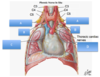

What are A-F?

A: coronary sinus

B: fossa ovalis

C: tricuspid valve

D: chordae tendinae

E: papillary muscles

F: trabeculae carnae